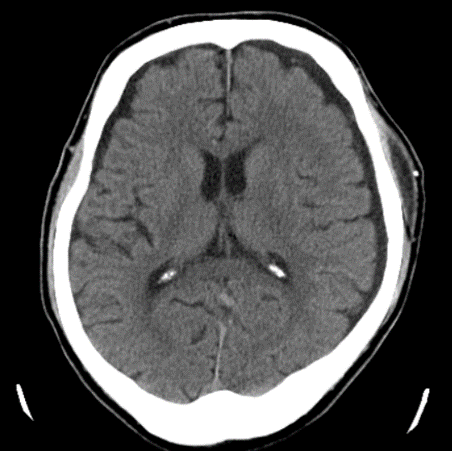

穿頭(せんとう)血腫除去術後

血腫は除去されている

術後から症状は改善され、退院。